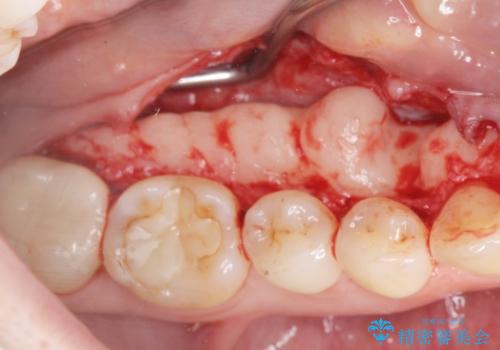

下顎隆起を切除することで舌を収めるスペースを確保し発音のしやすさの向上を図ります。

手術は約1時間弱で終了し、術後もほとんど腫れは出ません。